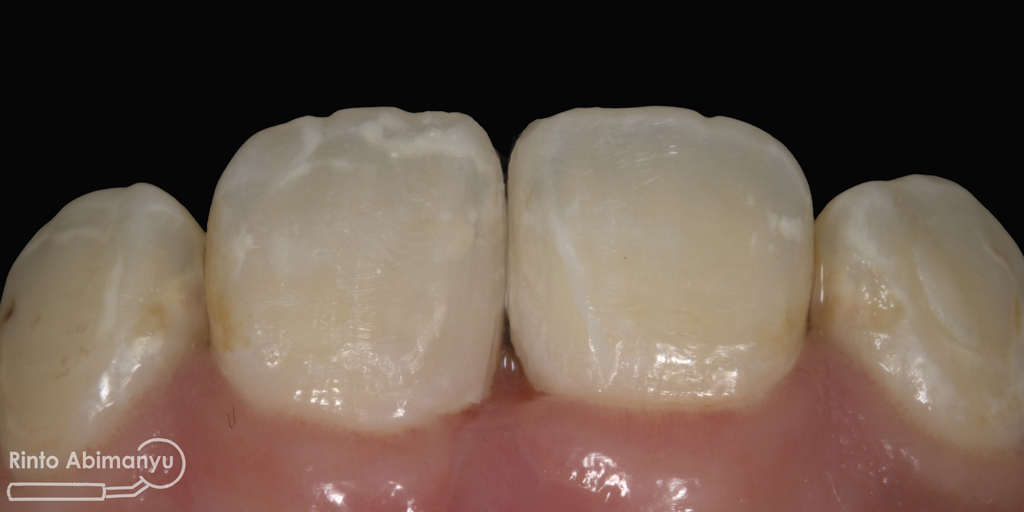

Setalah pengisian usahakan kamar pulpa dibersihkan dari sisa2 siler dan kotoran2 agar bahan adhesive yang kita pakai untuk restorasi dapat melekat maksimal.. Untuk basis saya menggunakan X-tra Base (Voco) kemudian diatasnya memakai komposit Z 350 XT (3M)…